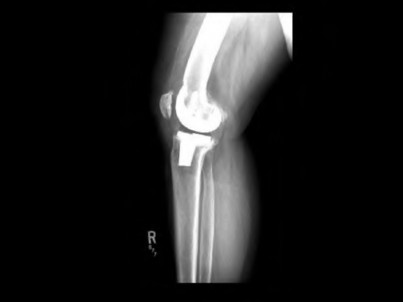

A 67-year-old diabetic male presents 4 months status post right total knee arthroplasty (TKA) complaining of pain and stiffness for the last four weeks. A clinical photograph is shown in Figure A. Radiographs and a bone scan are shown in Figures B, C and D. Blood work shows an ESR of 14mm/hr (normal 0-12mm/hr) and a CRP of 2mg/L (normal 1-3mg/L). Knee aspiration yields WBC of 1000, 30% PMNs, and a negative gram stain. He finished a 14-day course of antibiotics prescribed to him by his primary care physician one week ago. Which of the following is the most appropriate next step in management?

The work-up of a suspected PJI after TKA includes an evaluation of radiological (x-ray +/- bone scan and PET scan) and laboratory (ESR and CRP) parameters as well as analysis of joint aspirate fluid (cell count and differential, culture, gram stain +/- PCR).

Figure A is a clinical photograph demonstrating a swollen, erythematous right knee with a well-healed incision from a previous TKA. Figure B and C are AP and lateral radiographs of the right knee with no obvious acute findings. Figure D is a bone scan demonstrating increased uptake in the post-operative knee, which is consistent with the 4 month follow-up.